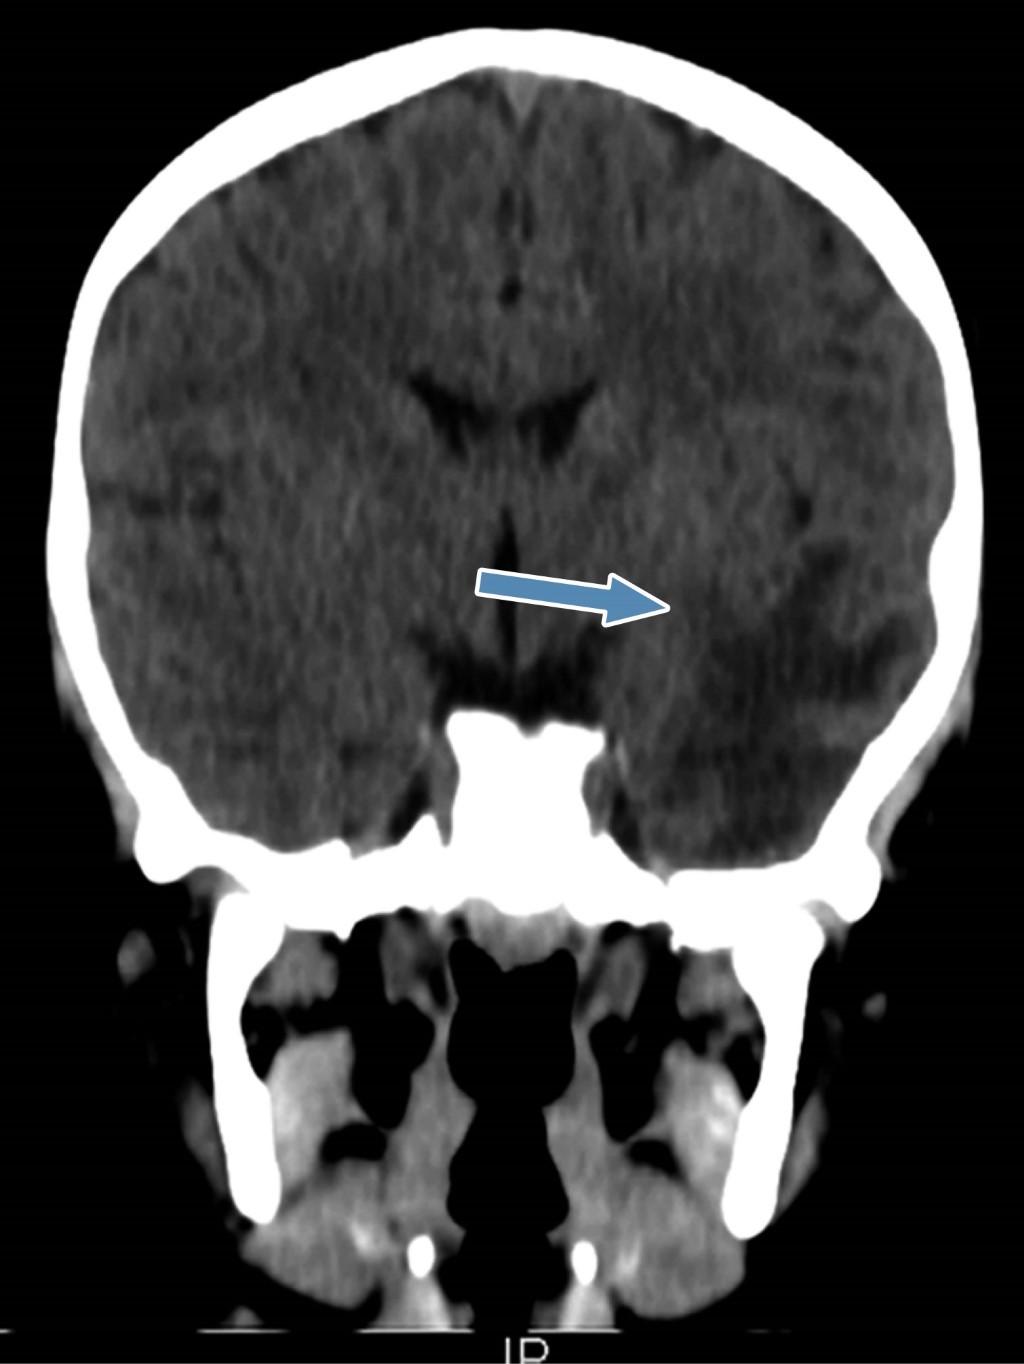

Al examen físico se evidenció otalgia izquierda asociada a dolor y aumento en la sensibilidad en la región mastoidea. Los exámenes solicitados revelaron leucocitosis (18.770/mm3) con neutrofilia, trombocitosis (628.000/mm3), elevación de reactante de fase aguda PCR 8.35 mg/dL (valores normales 0.10-0.30 mg/dL), elevación de ferritina 250.20 ng/dL (valores normales 7-140 ng/dL). Ante la alta sospecha de otomastoiditis, se inició terapia antibiótica intravenosa con ceftriaxona (100 mg/kg/día) y vancomicina (60 mg/kg/día). La paciente fue valorada por los servicios de neurología, neurocirugía e infectología; se solicitó estudio de imágenes y se realizó tomografía contrastada del cerebro, donde se evidenció una imagen hipodensa en el hemisferio izquierdo, compatible con absceso cerebral, además de signos de trombosis del seno sigmoideo izquierdo. En el corte de hueso mastoideo izquierdo se evidenciaron signos de hiperdensidad, confirmándose la otomastoiditis (Figura 1). Debido a ello, se solicitó resonancia magnética de cerebro (Figura 2), así como venografía cerebral (Figura 3), evidenciándose el absceso en el lóbulo temporal izquierdo, rodeado por edema perilesional y ausencia de flujo sanguíneo en el seno venoso transverso y sigmoideo izquierdo.

Figura 1